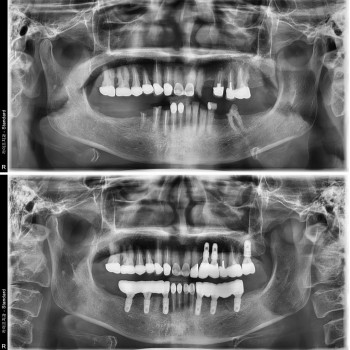

전체 임플란트 수술 케이스 전/후 사진

풀아치임플란트 소수의 임플란트로 전체 치료가 가능

20